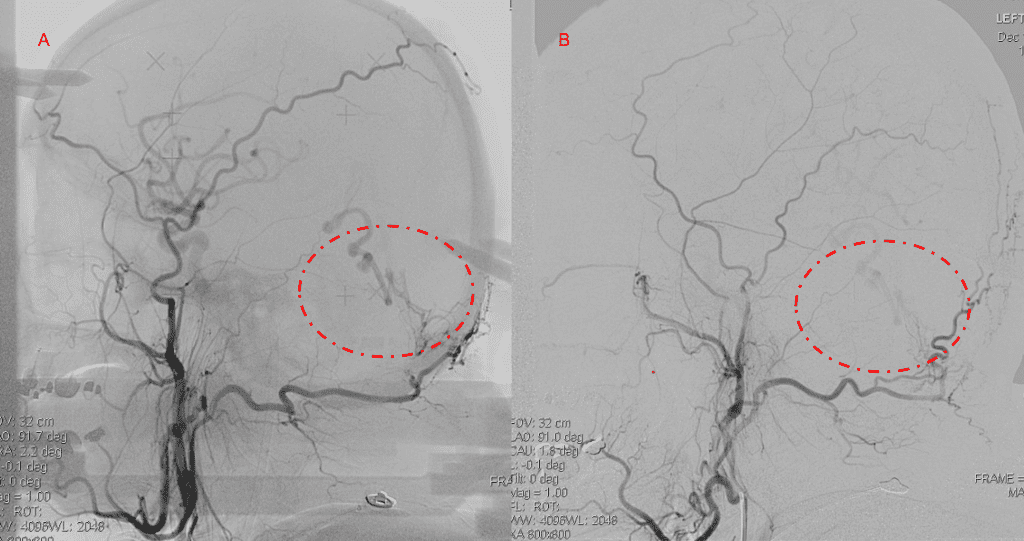

Figure 4. Left ECA AP and Lateral angiograms Pre (A and B) and Post NBCA embolization (C and D) Demonstrate near complete obliteration of Left Occipital Artery Fistulas.

Embolization was successful at immediately reducing the pressure into the Aneurysmal Varix with greater than 90% reduction in A-V shunts. After an intensive period of critical care monitoring and care for her initial brain hemorrhage, she made a near complete recovery with mild intermittent left sided paresthesias and generalized deconditioning. After receiving inpatient and outpatient Acute Rehabilitation, Physical, and Occupational therapy, she completely recovered all of her Activities of Daily Living (ADLs) at 3 months and achieved an modified Rankin Scale (mRS) of 0. On follow-up angiography, small residual low flow A-V shunts were identified and targeted for Gamma Knife Radiosurgery (Figure 5 and 6).